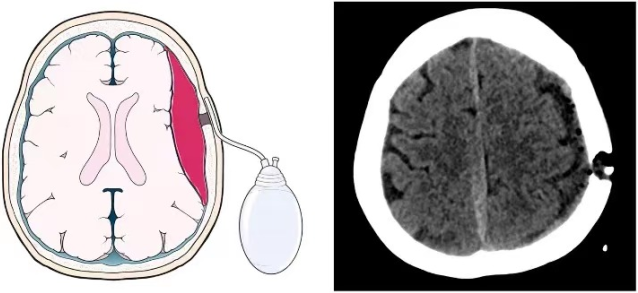

82岁的周奶奶(化名)近期出现神志恍惚、寡言少语、肢体无力、行走困难甚至小便失禁,家人起初误以为是“老年痴呆”。症状加重后送至贵州航天医院,经影像检查确诊为“慢性硬膜下血肿”。颅内较大血肿压迫脑组织,导致了这些神经功能损害。我院神经外科团队采用“微创引流”手术成功清除了血肿。术后1周,周奶奶康复出院;术后1月复查显示,受压脑组织复位良好,血肿无复发。 常见诱因与特点 该病多见于伴有脑萎缩的老年人,轻微头部外伤(如晃动、颠簸)即可撕裂脑表面脆弱的小静脉,造成缓慢出血,在脑萎缩、低颅压等因素影响下,血肿可能逐渐增大。典型症状包括记忆力减退、反应迟钝、嗜睡、肢体乏力等,易被忽视或误诊。 科学应对方案 少量无症状: 可尝试药物治疗,定期复查头部CT监测变化。 血肿增多或症状明显: 需及时就诊,颅骨钻孔微创引流术是首选且成熟的手术方式,能有效清除血肿、解除压迫。 防治复发: 脑膜中动脉栓塞术是预防复发的有效辅助手段。 温馨提示 老人轻微磕碰后若逐渐出现上述症状,应警惕慢性硬膜下血肿,即使受伤后早期颅脑CT未见异常,症状出现也需及时复诊,与高血压脑出血不同,慢性硬膜下血肿若能及早发现并规范治疗(如微创引流),通常预后良好。 注:部分图片来源于网络,如有侵权,请联系删除。 贵州航天医院 神经外科专家简介 廖洪民 神经外科党支部书记、主任,主任医师 临床擅长:从事神经外科临床工作30年,对颅脑损伤、脑肿瘤、脑血管病等具有丰富诊疗经验,擅长救治重症颅脑创伤、脑出血微创治疗、脑肿瘤显微手术治疗、脑立体定向手术等。 中国医师协会神经外科分会专科认证医师、贵州省医学会神经外科分会青年委员、遵义市医学会神经外科分会常务委员、遵义市中西医结合学会脑心同治专业委员会常务委员、中国生命关怀协会脑卒中救治及康复照护专业委员会委员、贵州省脑损伤评价质控中心专家库成员、遵义市脑损伤评价医疗质量控制中心专家。 朱家伟 神经外科副主任医师 临床擅长:从事神经外科工作26年,擅长颅脑损伤救治及脑出血微创手术。 遵义市医学会神经外科分会委员、遵义市中西医结合学会脑心同治专业委员会常务委员。 黄建军 神经外科副主任医师 临床擅长:从事神经外科工作20年,对神经外科常见病、急危重症有丰富诊疗经验,熟练掌握神经外科微创手术。 贵州航天医院 神经外科简介 基本情况 贵州航天医院神经外科于2008年独立建科,是首批国家卫健委能力建设和继续教育神经外科建设中心,贵州省神经外科介入联盟单位。现有专业技术人员17人,其中高级职称4人,中级5人,初级7人。 科室配备STORZ神经内镜系统、德国莱卡手术显微镜,国产西山开颅动力系统、蛇牌双极电凝、Mayfield头架等颅脑手术设备,以及无创和有创颅内压监护仪、正中神经刺激仪、脑循环康复治疗仪、排痰机、下肢康复训练器、气垫床、多参数监护仪等现代化医疗设备,为病区各种急、危、重患者的观察、监护和治疗保驾护航。 专科特色 (一)脑出血微创手术治疗 应用范围:各种病因导致的自发性脑出血(高血压脑出血、脑淀粉样血管病相关脑出血、抗凝药物相关脑出血等)。 技术优势:微创、精准、恢复快。 (二)颅脑病变显微切除术 应用范围:颅内各种占位性病变(脑囊肿、脑肿瘤等)。 技术优势:精确度高、创伤小、恢复快。 (三)颅脑创伤综合救治 应用范围:各种类型的颅脑损伤、创伤性颅内血肿及颅脑创伤并发症、后遗症等。 技术优势:快速精准诊断、个体化手术与监护、早期康复干预,伤者病死率低、并发症少。